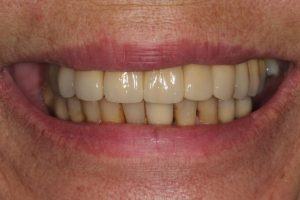

Full Mouth Rehabilitation

Full mouth Treatment – missing upper front teeth and mispositioned implants in the Lower left side meant planning was key here to get the desired result. Implants were placed to replace the missing teeth, veneers/crowns on the remaining upper teeth allowing an improvement in overall shape and colour, and the implant crowns on the lower left were change to bring into the line of the bite.